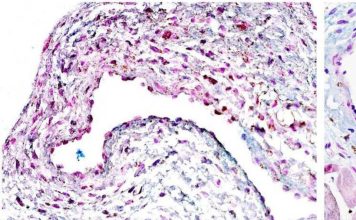

Inicio Tratamientos con células madre

Tratamientos con células madre